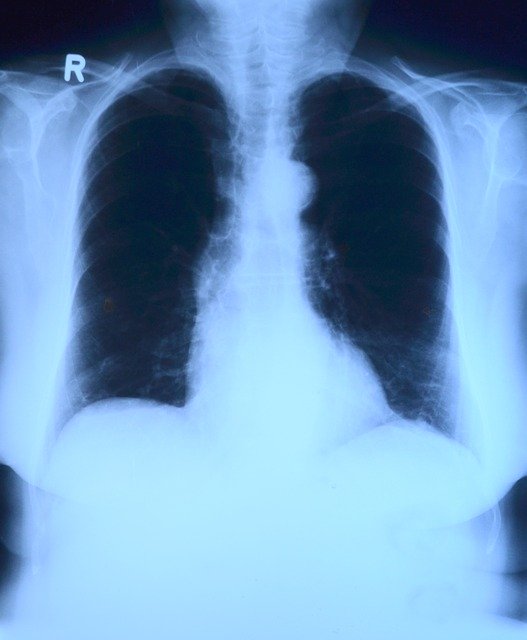

Investigadores del Hospital Gregorio Marañón, de la Universidad Carlos III, del Instituto de Investigación Sanitaria San Carlos y de la empresa Sedecal Molecular Imaging trabajan en el desarrollo de un nuevo sistema radiológico de alta precisión que serviría para mejorar el diagnóstico de los enfermos de coronavirus.

Los investigadores están combinando la Inteligencia Artificial (IA) y la tomosíntesis (con dosis bajas de rayos X) para desarrollar un dispositivo de bajo coste que podría aumentar sustancialmente la precisión diagnóstica radiológica, con niveles comparables a los que se consigue mediante un TAC.

Además, el sistema facilita la caracterización epidemiológica del brote, detectando mejor la existencia de afectación pulmonar y “simplifica” el trabajo al radiólogo. Y también garantiza la “optimización” de la dosis administrada al paciente. Además, ofrecería mucha mayor disponibilidad y sería más versátil, dado que se podría instalar incluso en vehículos o en carpas portátiles de triaje.

El proyecto, con una duración estimada de seis meses, pretende satisfacer la demanda generada por la pandemia de coronavirus mediante un sistema que facilita, además, la caracterización epidemiológica del brote, detectando mejor a existencia de afectación pulmonar.

El proyecto tiene una duración estimada de seis meses, al término de los cuales se pretende disponer de un nuevo sistema de radiología completamente funcional, capaz de realizar estudios “cuasi-tomográficos” de rayos X.